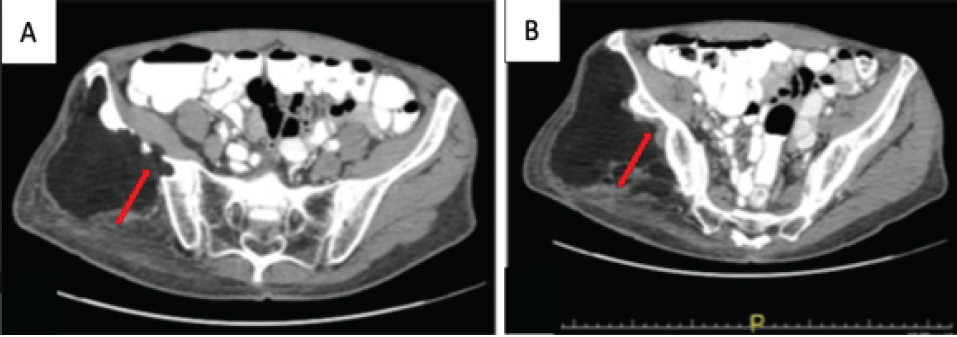

A 68 year-old man presented with a recurrent, non-painful mass in the right buttock. He had two prior resections at outside facilities. The first resection was of an intrapelvic mass performed 27 years before presentation through an anterior approach. The patient reported that this mass was a lipoma but no documentation of the histopathologic evaluation was available for review. The second resection was of a right buttock mass done 1 year before presentation through a posterior approach. Histopathologic interpretation of this mass at the outside hospital was that of a lipoma. Since the second resection, he noted a slow return of the mass along with pain in his right buttock that was associated with prolonged periods of sitting. On physical examination, there was a fullness of the right buttock with an apparent soft tissue mass that was soft and non-mobile. MRI demonstrated a mass that was hyperintense on T1 and T2 pulse sequences consistent with a lipomatous mass. The mass was predominantly in the buttock but extended through the sciatic notch into the retroperitoneal space (Fig. 2a). The majority of the mass appeared to be benign fat with some smaller areas with increased stranding. The mass abutted the posterior aspect of the ilium and appeared to have eroded through the posterior cortex in several places (Fig. 2b and c). There were no changes in the marrow adjacent to the erosions into the ilium. The changes in the ilium were better demonstrated on the CT scan with scalloping of the posterior ilium adjacent to the mass (Fig. 3a and b).

Figure 3: Case 2 computed tomography imaging findings – axial. (a and b) Demonstrates scalloping of the posterior cortex of the ilium by a large low attenuation mass (red arrow).